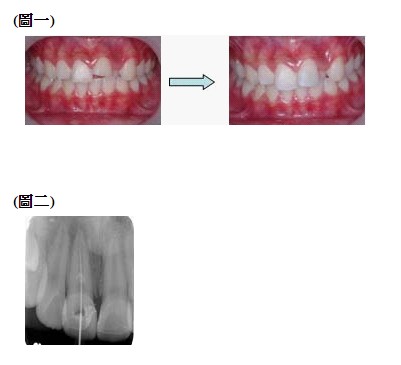

如果牙冠斷裂後,傷及牙髓神經時,應該適時將感染的牙髓清除乾淨,牙髓神經摘除時深度依照感染的狀況決定。

如曝露一點點時,只需摘除牙冠部份的牙髓組織即可(圖一)。

如果牙根尖已有病變,如(圖二)牙根尖已有感染,所以神經管會壞死,則整段神經管好好清除及封填。請家長不用擔心,

根管治療後的牙齒再加上牙冠的保護,仍可以使用很久的。